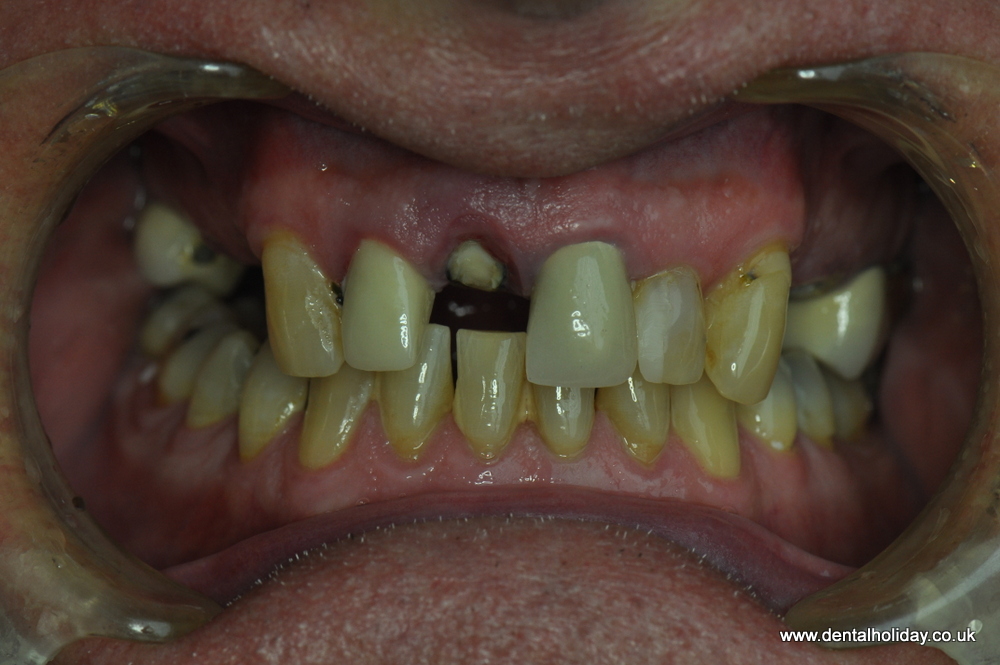

John was referred to us by his lovely sister, who recently had her dental treatment successfully completed with us in 2015. John had just a few missing teeth, but he noticed that existing teeth were breaking up over the past 12 months. He was therefore looking for a permanent solution, one that would last the rest of his days without having to visit the local dentist for continual repairs.

See the immediate change after first visit.